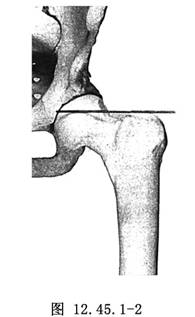

2.置入導針 在透視引導下,通過股骨頸向髖臼中心鑽入導針,要求導針與股骨幹軸線垂直(圖12.45.1-2)。如果有半脫位,該中心通常位於股骨頭中心的稍下方。